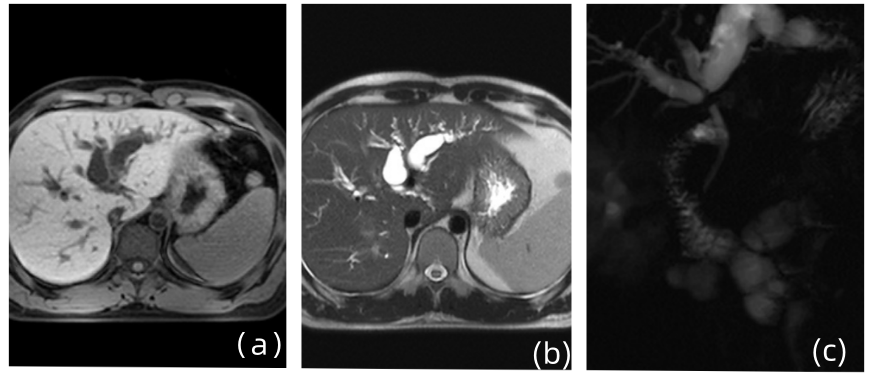

- Cell Rep Med:肠道准备可促进肠道内病原体定植和易位并加重炎症 本研究旨在探讨结肠镜检查前的肠道准备对肠道微生物群与肠道微环境的作用,并阐明在IBD背景下肠道准备对疾病发展的影响。……